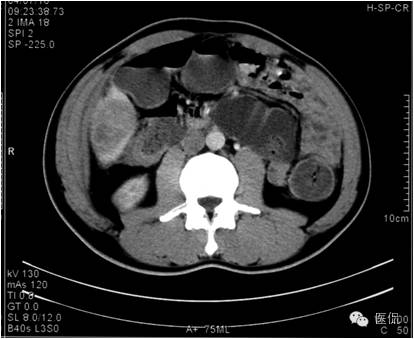

平扫示肝下缘局部隆突,密度减低,内部密度不均,隐约见分隔影,其下缘与升结肠界线消失,肠壁增厚、模糊。